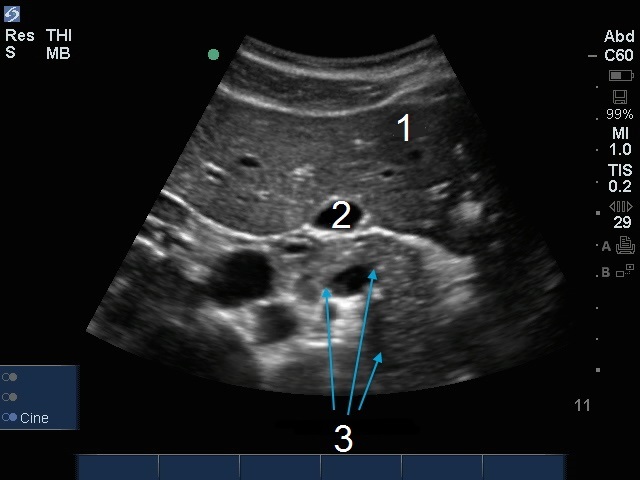

胆嚢脾臓画像

肝臓

胆嚢(GB)

膵臓横断